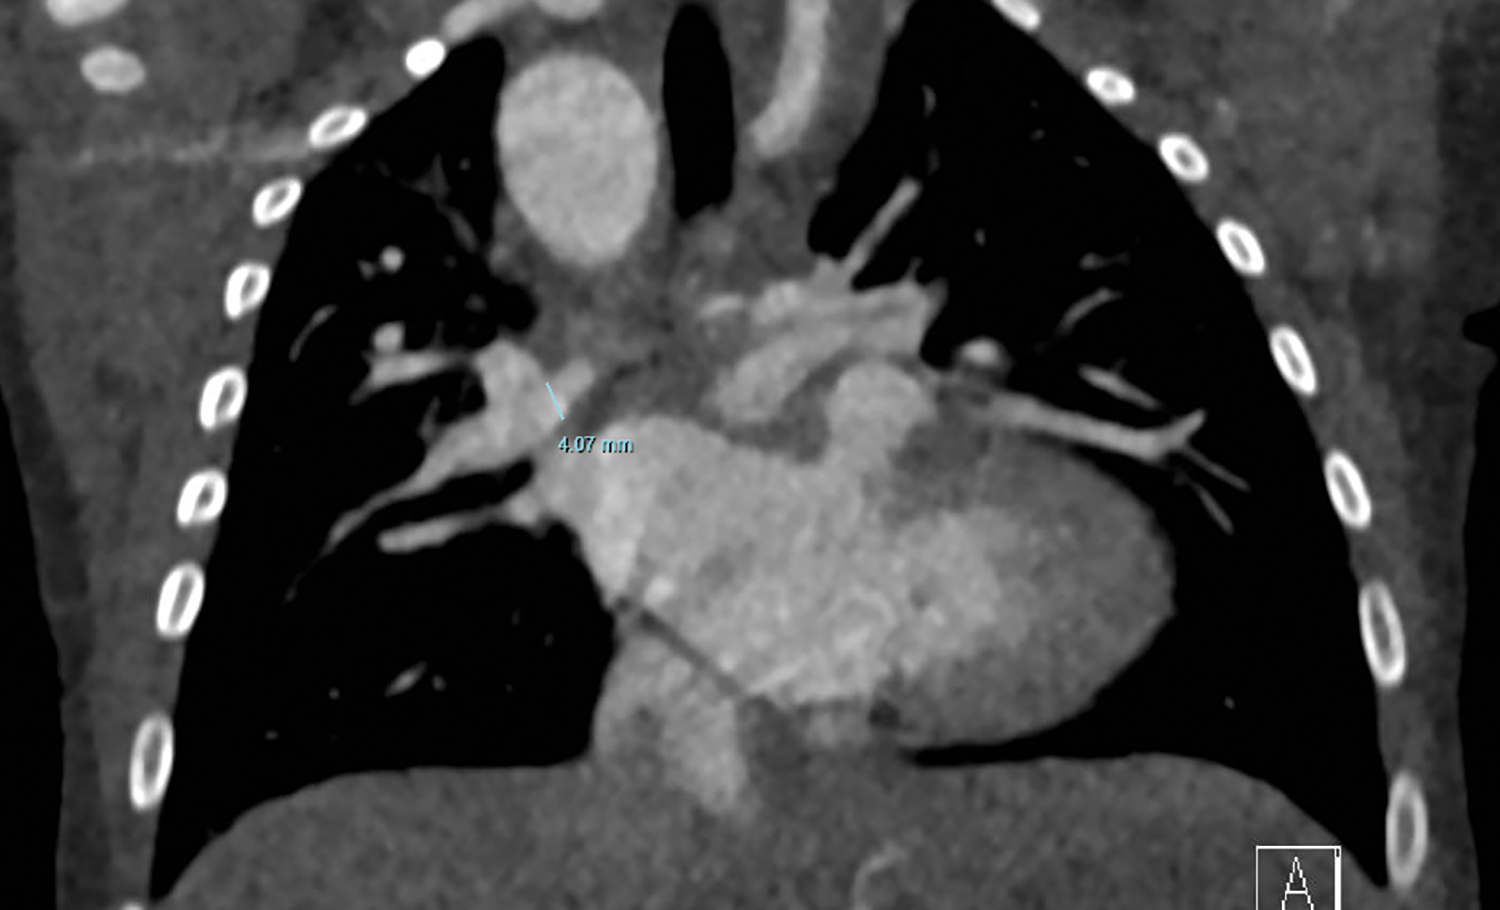

Demographic and medical data were collected retrospectively from medical records. Follow up was complete. Angiographic studies and CT imaging (in 4 patients) were used to measure the size of right (RPA) and left pulmonary artery (LPA) just proximal to the origin of the first branch, see Fig. 2 [17]. Since 2015 (the last four patients in this cohort), we routinely applied CT imaging as first diagnostic tool instead of angiography in these patients, often in the newborn period. Measurements were done prior to the Melbourne shunt and prior to further unifocalization. The measurements at the two time-points were related to body size by calculating maximum pulmonary artery branch diameter in mm/body surface area in m2. Also z-scores were calculated before and after shunt surgery.

Figure 2: CT image with measurement of RPA